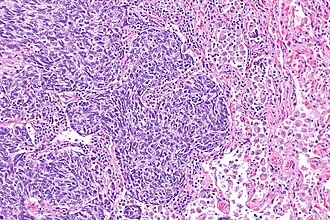

Atypical lung carcinoid tumour. H&E stain.

Features:[4]

• Nests of cells.

• Stippled chromatin.

• Mild-to-moderate amount of cytoplasm.

• No necrosis/focal necrosis.

• Moderate mitotic rate (2-10/HPF - definition suffers from HPFitis).